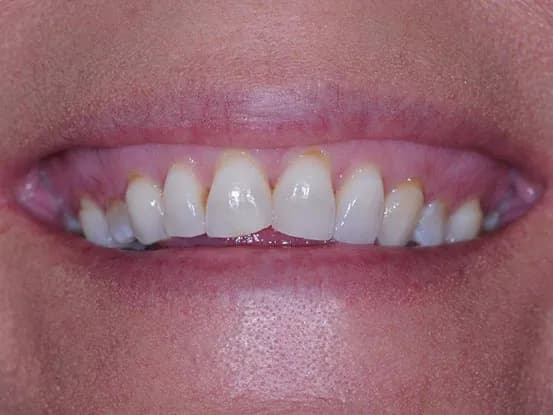

Case 1

26 year old female with teeth crowding and slight overbite. Patient refused to have 2 years of orthodontics. Gingivectomy, cosmetic bonding, extraction, Zoom Bleaching, and 12 units of e-max restorations performed.